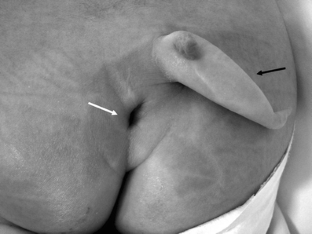

We present a female baby with a human tail associated with congenital dermal sinus (CDS) at the caudal site of the tail. Magnetic resonance (MR) images with constructive interference in steady-state (CISS) sequencing clearly demonstrated a lumbosacral lipoma of caudal type, contiguous with the dermal sinus tract and not with the human tail. At 3 months old, the tail was surgically removed. The dermal sinus tract and contiguous lipoma were also resected, and untethering of the spinal cord was performed. Although both the human tail and CDS are frequently associated with spina bifida occulta, coexistence of the tail and CDS is exceedingly rare. CISS-MRI is useful for demonstrating the precise anatomical relationship between these complicated pathologies.

Fig. 1